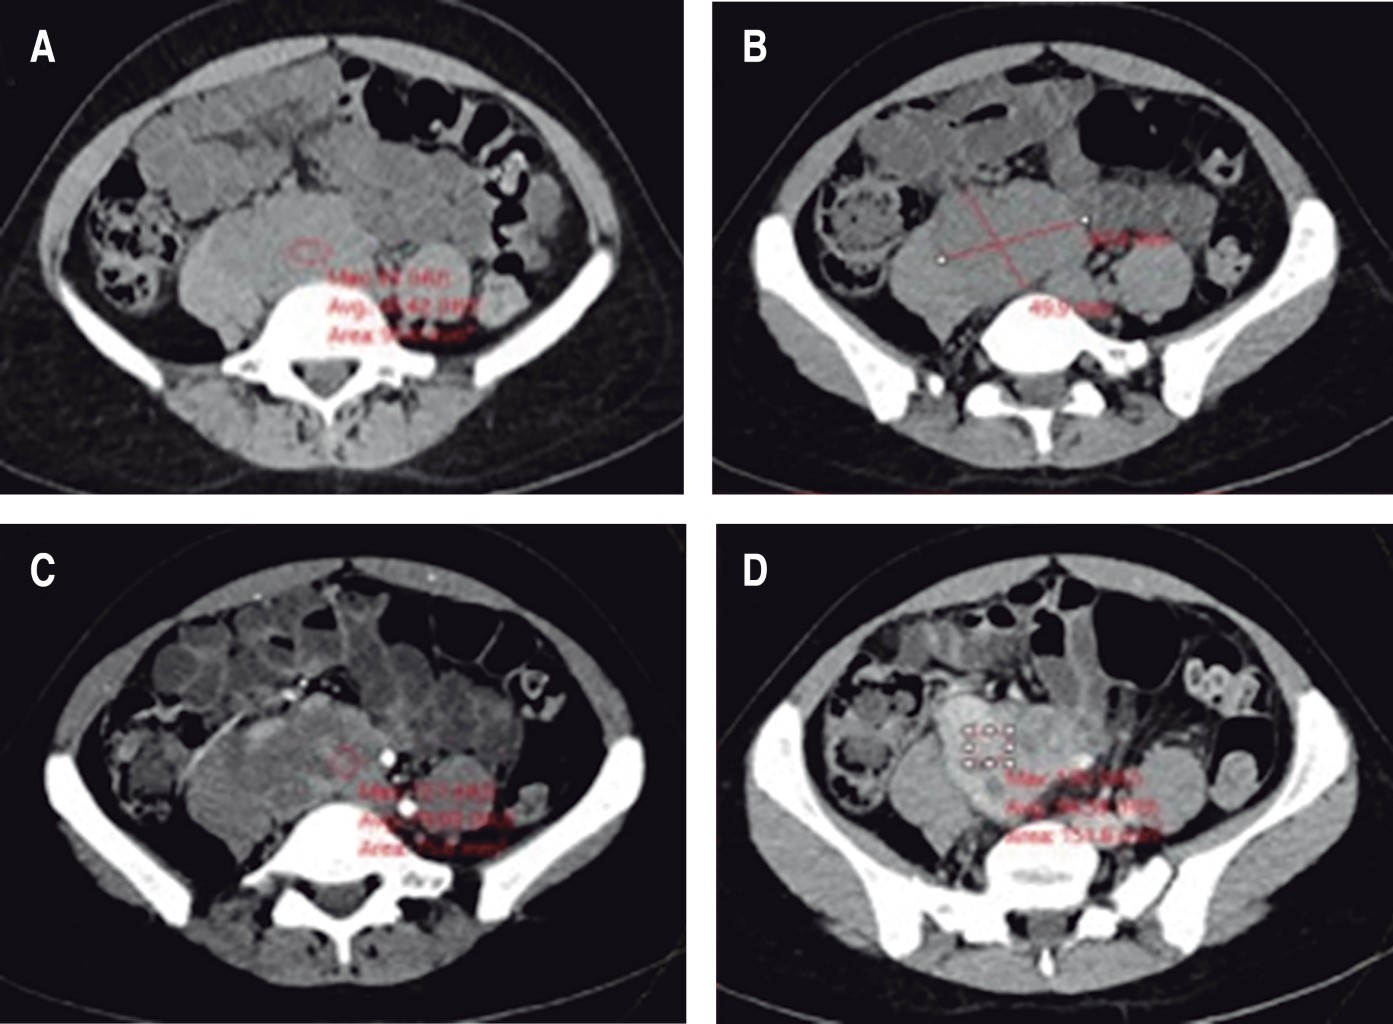

Se trata de paciente femenina de 35 años sin antecedentes personales patológicos de importancia; refiere iniciar su padecimiento actual en junio del 2020 con dolor importante en espalda baja, tolerable sin atenuantes ni agravantes, tratado con manejo conservador presentando mejoría parcial de la sintomatología. Meses después se incrementó la sintomatología, siendo el dolor más intenso y frecuente en el mismo sitio, además de irradiarse hacia ambas caderas y piernas. Acude a consulta para protocolo de estudio. Se solicitaron tomografía axial computarizada de abdomen en fase simple y con contraste endovenoso. Se identificó una lesión ocupante de espacio que se localiza en el retroperitoneo, infrarrenal, por delante y paramedial derecha de los cuerpos vertebrales L4 a S1; es de contornos lobulados, delimitada posterior y hacia la derecha por el músculo psoas y por los cuerpos vertebrales, los cuales se observan íntegros; ocasiona desplazamiento hacia ventral de la vena cava inferior y medial y hacia posterior de la vena iliaca derecha, desplaza hacia la izquierda las arterias iliacas primitivas. Su densidad promedio es de 45 UH en la fase simple y con el contraste endovenoso presenta reforzamiento heterogéneo con incremento del índice de hasta 79 UH en la fase arterial y de hasta 98 UH en la fase venosa y persiste con similares índices en la fase tardía de eliminación. Compromete el tránsito de contraste de la vena iliaca derecha y de la porción proximal de la vena cava inferior, las cuales no se logran distinguir, mientras que la vena iliaca izquierda muestra franco incremento en su diámetros y retorno lento del contraste. La lesión mide 62 mm en transverso, hasta 57 mm en diámetro anteroposterior y 49.9 mm en cefalocaudal (Figuras 1 y 2).

Figura 2